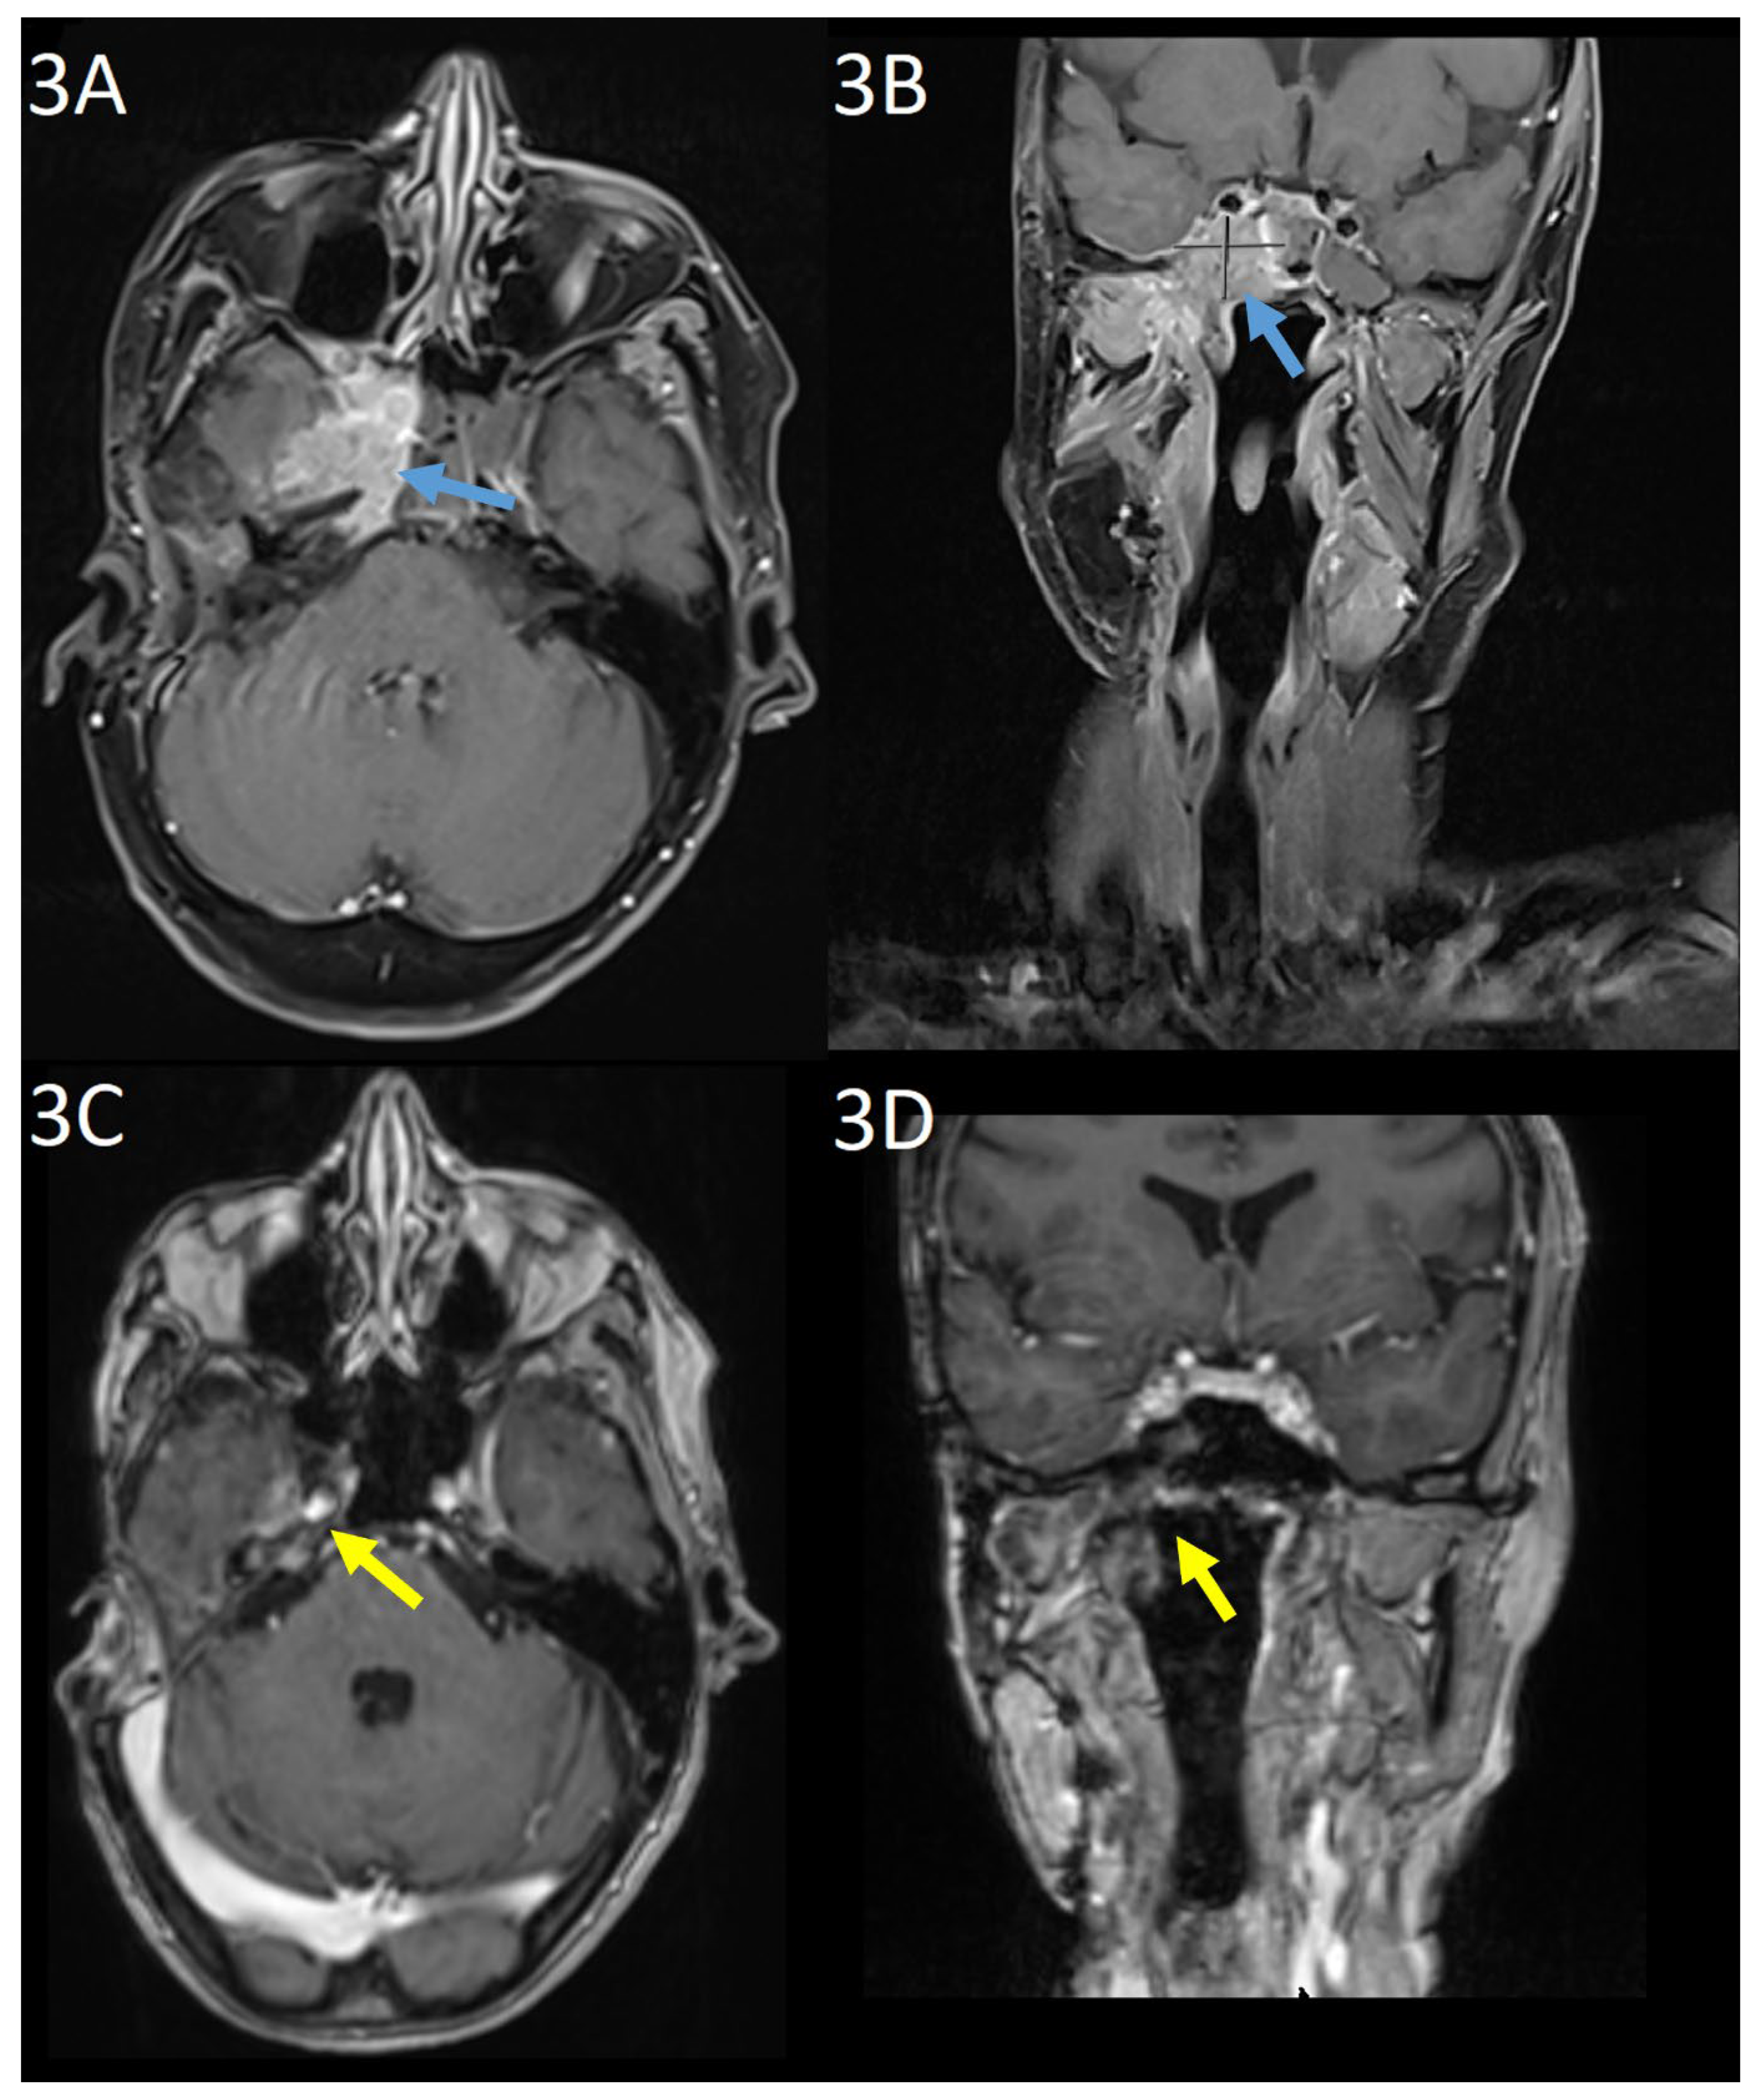

Baseline gadolinium-enhanced MRI head prior to commencing TDM1 showed unresectable tumour at the right cavernous sinus with involvement of the meninges, clivus, and petrous bone as well as the sphenoid sinus and masticator space (Figure 3(a) and 3(b)). CT with contrast did not demonstrate any distant metastases. Nuclear medicine cardiac ventriculography showed a left ventricular ejection fraction of 70%. Baseline symptoms were facial pain, paraesthesia of the right mandible, and unsteadiness. At this point, further surgery was not possible and three-weekly TDM1, 3.6mg/kg was commenced.

At three months, there was evidence of clinical and radiological response. Gadolinium-enhanced MRI showed the mass centred on the cavernous sinus had reduced from 3.5 x 2.5cm to 1.9 x 0.7cm. The patient reported improvement in mobility and resolution of the facial pain. Serial imaging then showed further reduction in disease through to 15 months, from which no measurable disease was visible on MRI imaging. This remained the case on MRI imaging at 38-months post-treatment (Figure 3(c) and 3(d)). Six-monthly nuclear medicine cardiac ventriculography has shown a stable ejection fraction throughout treatment. Nine months after commencing treatment, the patient developed a stable, grade 1 increase in aspartate aminotransferase with no concurrent increase in bilirubin, which continues to be monitored and is considered to be drug-related.

Figure 3. Gadolinium-enhanced MRI scan at baseline in (a) axial and (b) coronal planes and 38 months post-treatment in (c) axial and (d) coronal planes. The enhancing mass centred on the right cavernous sinus in (a) and (b) (blue arrows) is no longer apparent in (c) and (d) (yellow arrows).